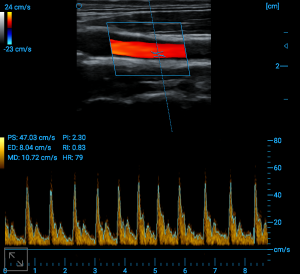

Carotid bulb blood flow

PW auto trace